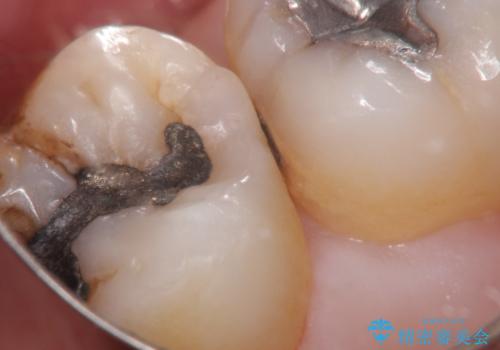

むし歯の治療。ゴールドインレーによる修復

- 定期健診にてむし歯を認めたためゴールドインレーにて治療を行いました。

拡大鏡で常に口腔内を診察しているため、小さなむし歯も見逃さずに治療を行っています。